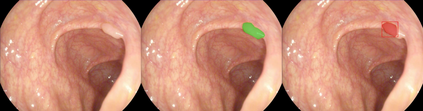

Early detection, accurate segmentation, classification and tracking of polyps during colonoscopy are critical for preventing colorectal cancer. Many existing deep-learning-based methods for analyzing colonoscopic videos either require task-specific fine-tuning, lack tracking capabilities, or rely on domain-specific pre-training. In this paper, we introduce \textit{PolypSegTrack}, a novel foundation model that jointly addresses polyp detection, segmentation, classification and unsupervised tracking in colonoscopic videos. Our approach leverages a novel conditional mask loss, enabling flexible training across datasets with either pixel-level segmentation masks or bounding box annotations, allowing us to bypass task-specific fine-tuning. Our unsupervised tracking module reliably associates polyp instances across frames using object queries, without relying on any heuristics. We leverage a robust vision foundation model backbone that is pre-trained unsupervisedly on natural images, thereby removing the need for domain-specific pre-training. Extensive experiments on multiple polyp benchmarks demonstrate that our method significantly outperforms existing state-of-the-art approaches in detection, segmentation, classification, and tracking.